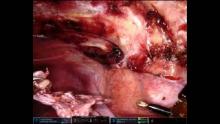

Robotic-Assisted Diaphragm Resection and Pleurectomy [1]

We present a case of a 40-year-old female who presented with cyclical abdominal pain and was subsequently diagnosed with endometriosis. Computed tomography scan of the chest revealed a 25mm nodule in the right hemidiaphragm, and she was therefore consented for robot-assisted diaphragmatic resection and repair and pleurectomy to prevent possible catamenial pneumothorax. We initially approached the diaphram using 3 robotic ports and 1 assistant port in a pelvic position (1). Once the endometrial deposits were removed, the diaphragm was repaired with an Ethibond stitch and patch repair was subsequently undertaken. The robot was then undocked and repositioned via the same ports in the normal thoracic approach, before undertaking extensive pleurectomy. The patient made a full recovery and was discharged home on post-operative day 3 without complication.